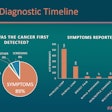

Many young women with breast cancer symptoms delay care

April 12, 2024